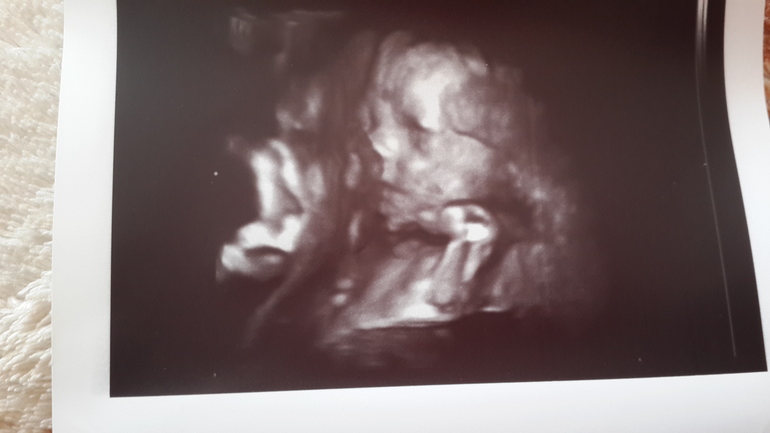

26+6, наше УЗИ)))

УЗИ, КТГ, доплерСходила на внеплановое узи, посмотрела своего кроху😊 все показатели в норме, развитие согласно сроку 27 недель)) БПР 68 мм, ЛЗР 87мм. Окружность головы 251 мм. Длина бедренной кости 50,7мм(на прошлом узи была коротковата-сейчас в норме!). Все органы развиваются хорошо, ЧСС 140 уд/мин. Лежит малыш поперек (Софья на таком сроке тоже поперек была☺ - надеюсь, перевернется как надо ближе к родам). Предполагаемый вес поставили 1094 гр. Моё чудо килограммовое))) думала меньше будет😁

А вот и фото нашего крохи

на носик попал фрагмент пуповины))) лежит кнопик наш, ручкой щечку подпирает😊😍😍😍😍😍